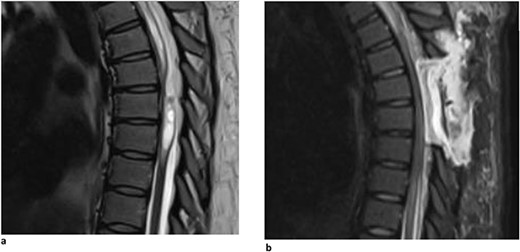

A 67-year-old man presented with a 1-year history of midline back pain that radiated down his right side and myelopathic symptoms. He stated that his symptoms worsened over the last year, and he felt generally weak in the lower extremities, causing problems with ambulation. He did not have any bowel or bladder incontinence, and there was no history of spinal surgery or syrinx expansion. MR imaging demonstrated a spinal cord indentation along the dorsal surface of the spinal cord at the T5 vertebral body level (Fig. 1a). It was hypothesized that the appearance of the spinal cord indentation was secondary to an arachnoid web. The patient underwent T5-T6 laminectomies for intradural exploration for arachnoid web resection at the level of the spinal cord narrowing. The arachnoid web was inspected, and the area of tether was identified and removed using microsurgical tools and technique (Video S1). Postoperatively, the patient reported improvement in back pain, increased strength within the lower extremities, and mild chest wall numbness. Follow-up MR imaging demonstrated resolution of the dorsal indentation and cord expansion (Fig. 1b).

(a) Dorsal indentation (scalpel sign) demonstrated in thoracic spine preoperatively (Patient A). (b) Postlaminectomy and resection of posterior arachnoid web demonstrating resolution of dorsal indentation and cord signal changes (Patient A).